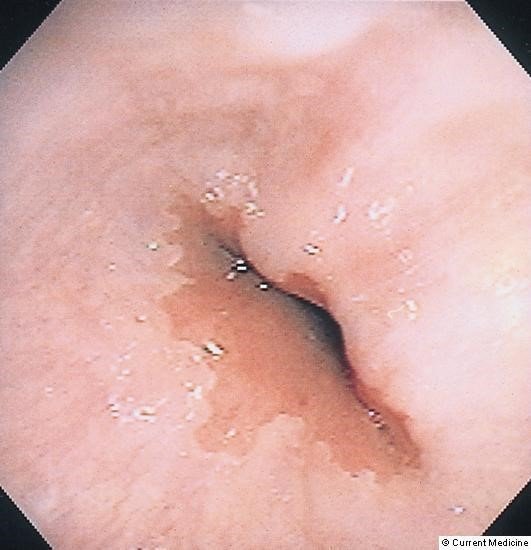

Diaqnozun dəiqiləşdirilməsi üçün kontrastlı Rentgenoloji müayinələr, KT və çox ehtiyatla endoskopiya edilir.

- Kontrastlı Rh-qrafiya - diaqnozu dəqiqləşdirən müayinədir.

- Endoskopiya - divertikulun perforasiyası təhlükəsinə görə çox ehtiyatla aparılmalıdır.

- Rentgenoqrafik divertikul görünməsi